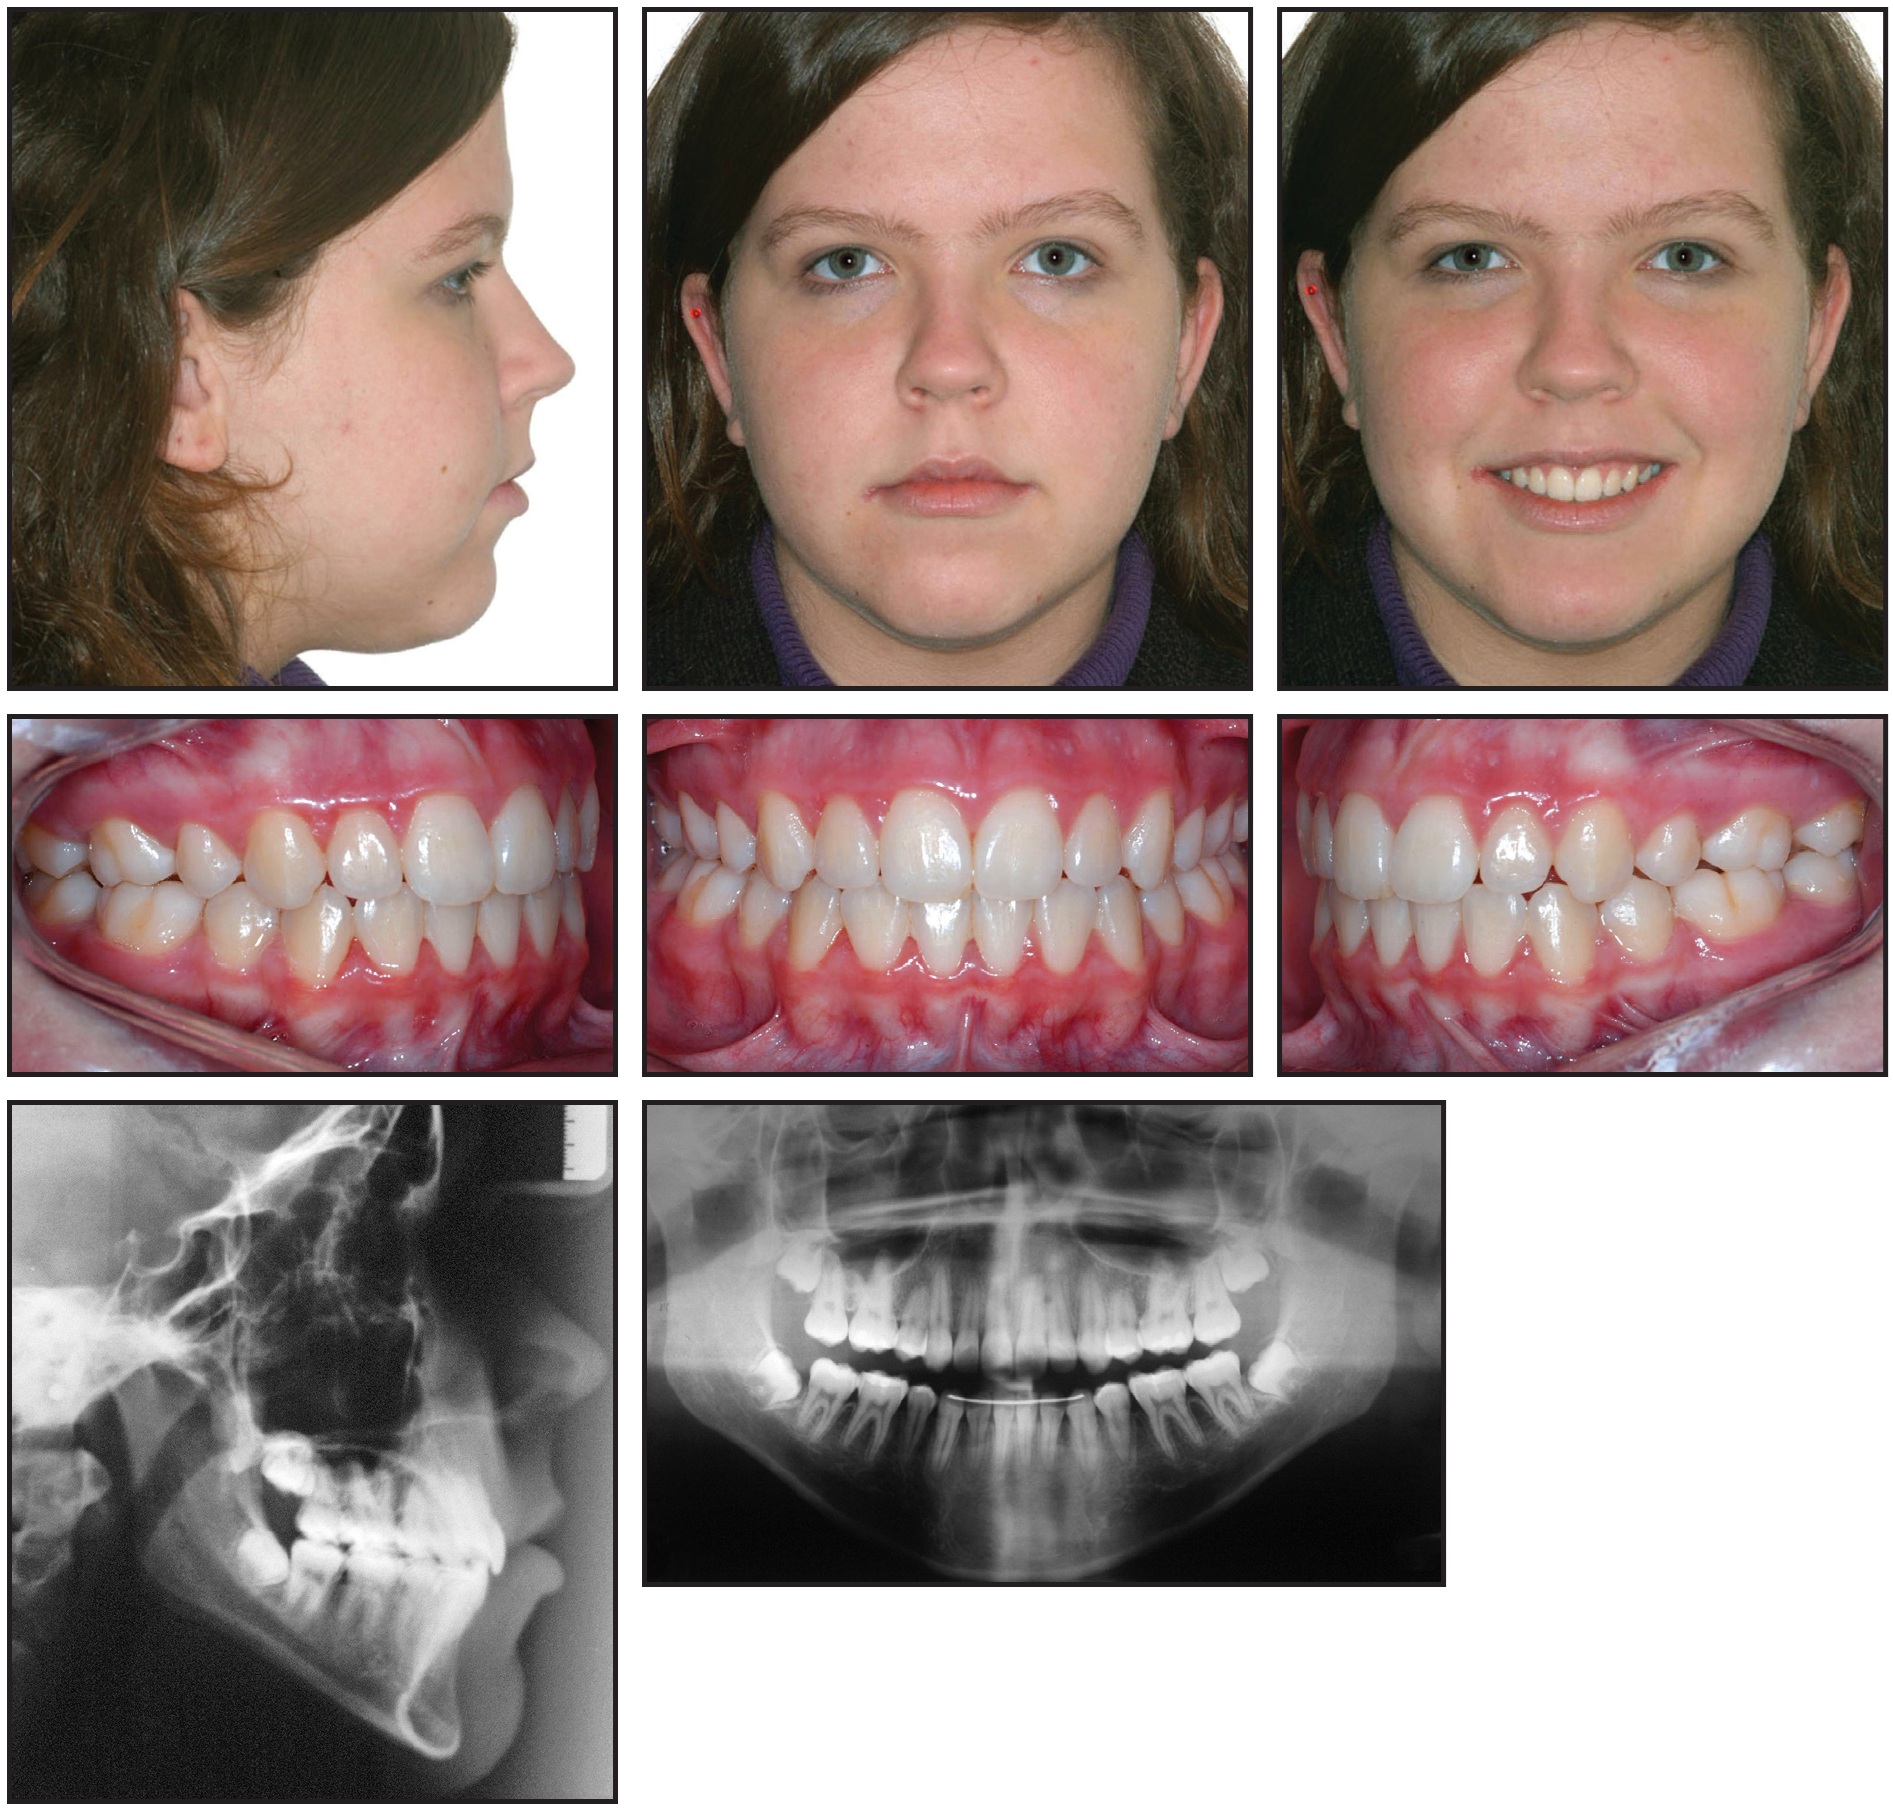

All treatment goals were achieved during these two stages. Extraction of the first premolars and agenesis of the lower second premolars permitted retraction of the anterior teeth, which improved facial harmony and lip posture. The midline deviation and Class II malocclusion were also corrected, and adequate overjet and overbite were obtained. The final panoramic radiograph showed acceptable root parallelism and integrity, with the upper and lower incisors better positioned in their bony bases (Table 1). The overall trend of facial growth remained vertical.

Extraction of the third molars was requested. Four years after treatment, the occlusion and facial appearance remained stable, and the patient was fully satisfied with the results (Fig. 5).

Fig. 5 Patient four years after treatment.